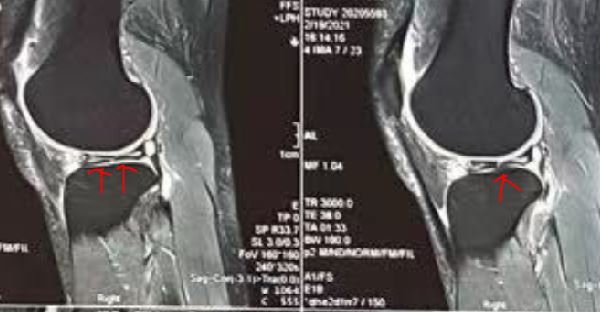

1 核磁共振显示外侧半月板横裂(横断);关节镜下可以清晰可见外侧半月板横断

2 核磁显示外侧半月板横(斜)裂,关节镜下可以清晰看到半月板损伤的位置

3 核磁显示外侧半月板撕裂为层裂(相当于半月板内部撕裂,分层),从而引起更加明显的症状;关节镜下可以看到半月板上下两层分离

4核磁显示外侧半月板撕裂形成囊肿,膝关节周围压痛明显,有时候囊肿可以很大,压迫周围组织;关节镜下可以看到半月板囊肿的位置